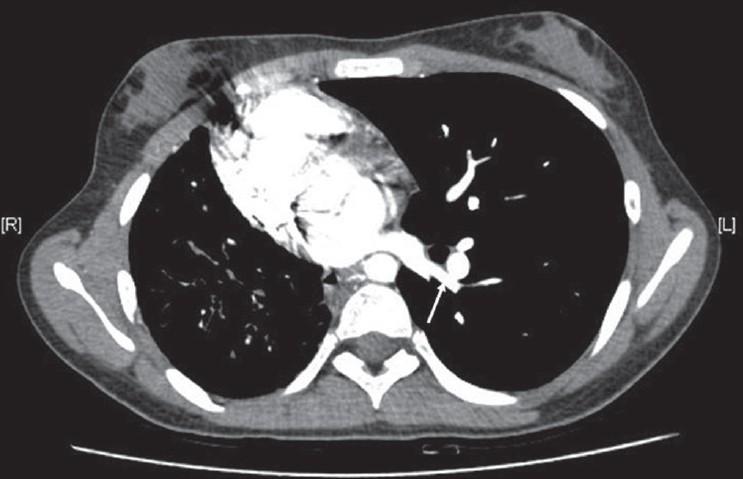

Scimitar syndrome is a rare congenital disorder. It has a varied presentation. In adult life, it usually presents either as recurrent chest infection and/or exertional dyspnea. Pulmonary artery hypertension and hemoptysis both are uncommon features of this syndrome in adult life.

弯刀综合征是一种罕见的先天性疾病。其表现多样。在成年期,它通常表现为反复的胸部感染和/或劳力性呼吸困难。肺动脉高压和咯血在成年期都是该综合征不常见的特征。